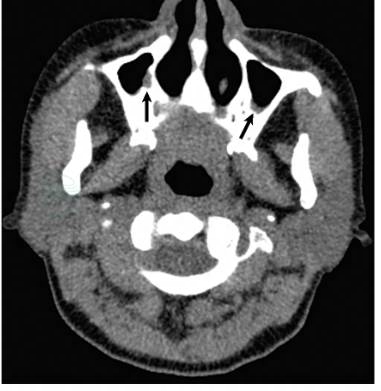

鼻窦CT(图3):双侧上颌窦局部黏膜增厚,考虑鼻窦炎。

图3 鼻窦CT示:双侧上颌窦局部黏膜增厚(黑箭)

引自:主编:.呼吸与危重症医学疑难与危重病例精选.第1版.ISBN:978-7-117-30147-3